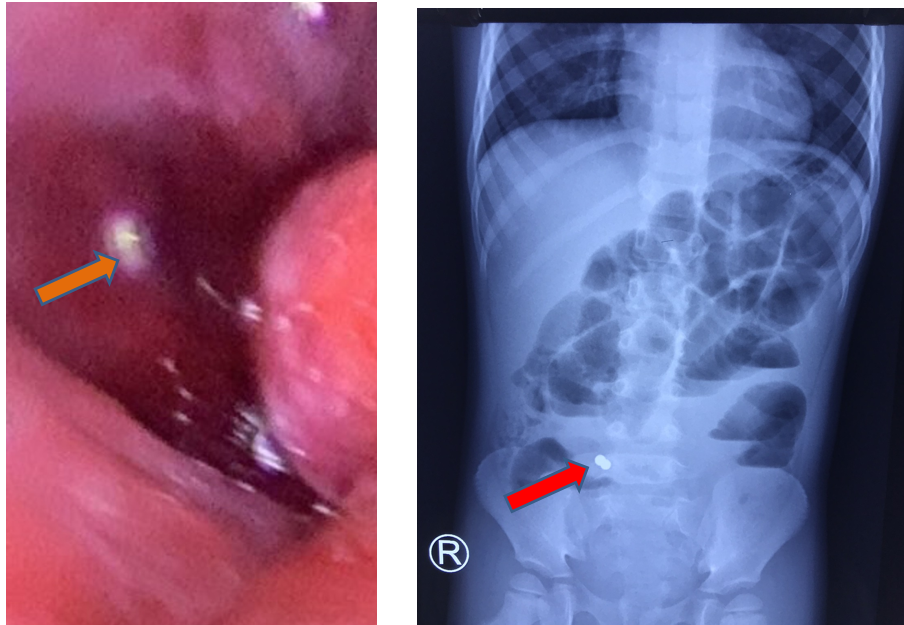

Lúc 16 giờ 08/05/2021, bệnh viện Nhi đồng Thành phố tiếp nhận một trường hợp trẻ Tr. K. Ng 3 tuổi, nữ, ngụ ở Long An, nhập viện trong tình trạng đau bụng, nôn ói nhiều. Bệnh sử ghi nhận cách nhập viện 2 ngày, trẻ đau bụng, kèm ói 5-6 lần, không đi tiêu, được khám bác sĩ tư, chẩn đoán rối loạn tiêu hóa, điều trị men tiêu hóa, thuốc chống nôn, tình trạng không cải thiện, trẻ đau bụng nhiều, ói nhiều ra dịch xanh nên nhập viện Nhi đồng Thành phố. Tại đây trẻ được các bác sĩ thăm khám, xét nghiệm, chẩn đoán hình ảnh Xquang bụng đứng không sữa soạn cho thấy có hình ảnh mực nước hơi kèm dị vật kim loại theo dõi pin hoặc nam châm, nên được hội chẩn bác sĩ ngoại khoa chuyển phòng mổ tiến hành phẫu thuật nội soi ghi nhận các quai hỗng tràng dãn, thành dày. Tại hố chậu phải có một vài quai ruột tím bầm. Gỡ dính, bộc lộ vị trí tắc thấy có 2 viên bi nam châm đường kinh # 1cm, từ hai quai ruột khác nhau đang hút vào nhau gây thủng ruột tại vị trí tiếp xúc. Mở rộng trocar rốn. Đưa 2 quai ruột chứa hai viên nam châm ra ngoài, lấy dị vật, thành ruột phù nề, xuất huyết, tím nhạt, cho ruột vào lại ổ bụng. Nội soi kiểm tra từ gốc hồi manh tràng: vị trí thủng thứ nhất cách van hồi manh tràng 30cm và vị trí thủng thứ 2 cách van hồi manh tràng 100cm xén chỗ hoại tử và khâu vá 2 lỗ thủng 2 lớp. Sau mỗ hiện tại trẻ tỉnh, môi hồng/khí trời, không sốt, sinh hiệu tạm ổn, bụng mềm không chướng, được điềua trị dịch truyền dinh dưỡng, kháng sinh, giảm đau. Được biết trẻ được ông ngoại nuôi giữ trẻ vì ba mẹ đi làm hàng ngày, trẻ chơi với búp bê điện tử, bên trong có các viên bi nam châm, nên trẻ tháo lấy ra nuốt vào đường tiêu hóa mà gia đình không hay biết.